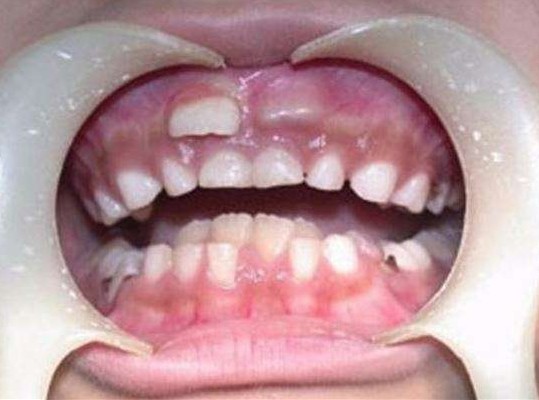

來自湖北武漢的黃女士最近非常擔心兒子,因為正在換牙的兒子竟長出了「雙排牙」。

黃女士的兒子「樂樂」今年8歲,他同學從6歲開始就陸續換牙了,他卻一直沒動靜,直到8歲後他才出現換牙的情形。由於舊的乳牙沒及時脫落,而下排牙齒中間長出的兩顆新牙,被擠在一起了,中間還有半顆牙的空隙,看上去就像長了雙排的異形牙。醫生看過後,說這是兒童常見的狀況,但是責任是在家長身上。

醫生表示雙排牙的孩童情形越來越多。